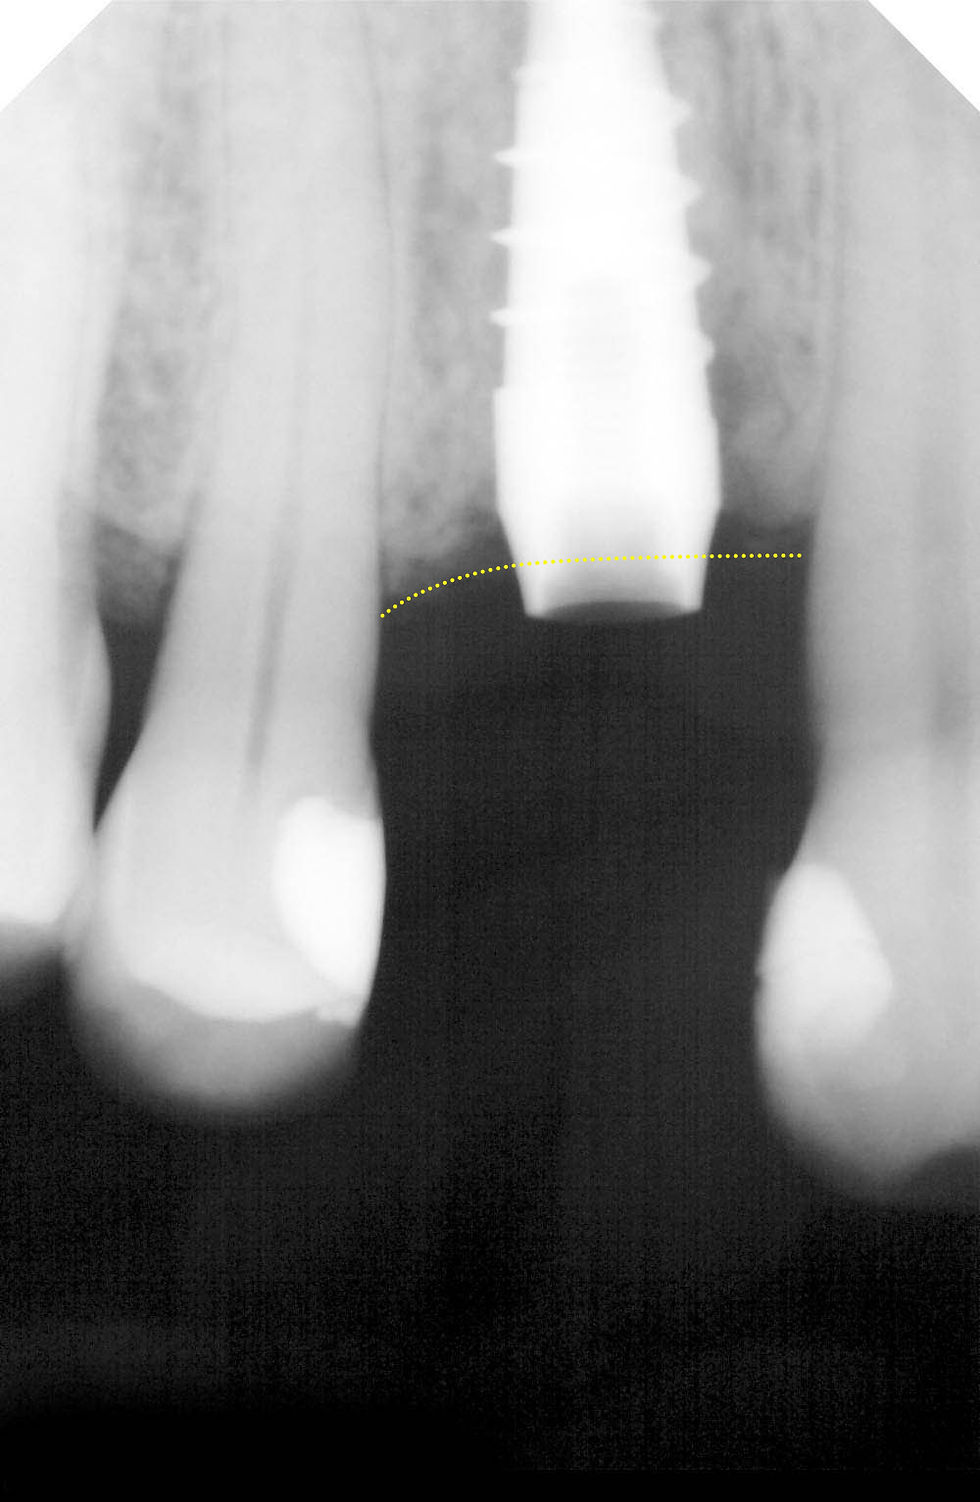

Radiographic control during implant insertion, to manage the irregular progression of the bone crest with the 2.8 mm neck of Prama RF.